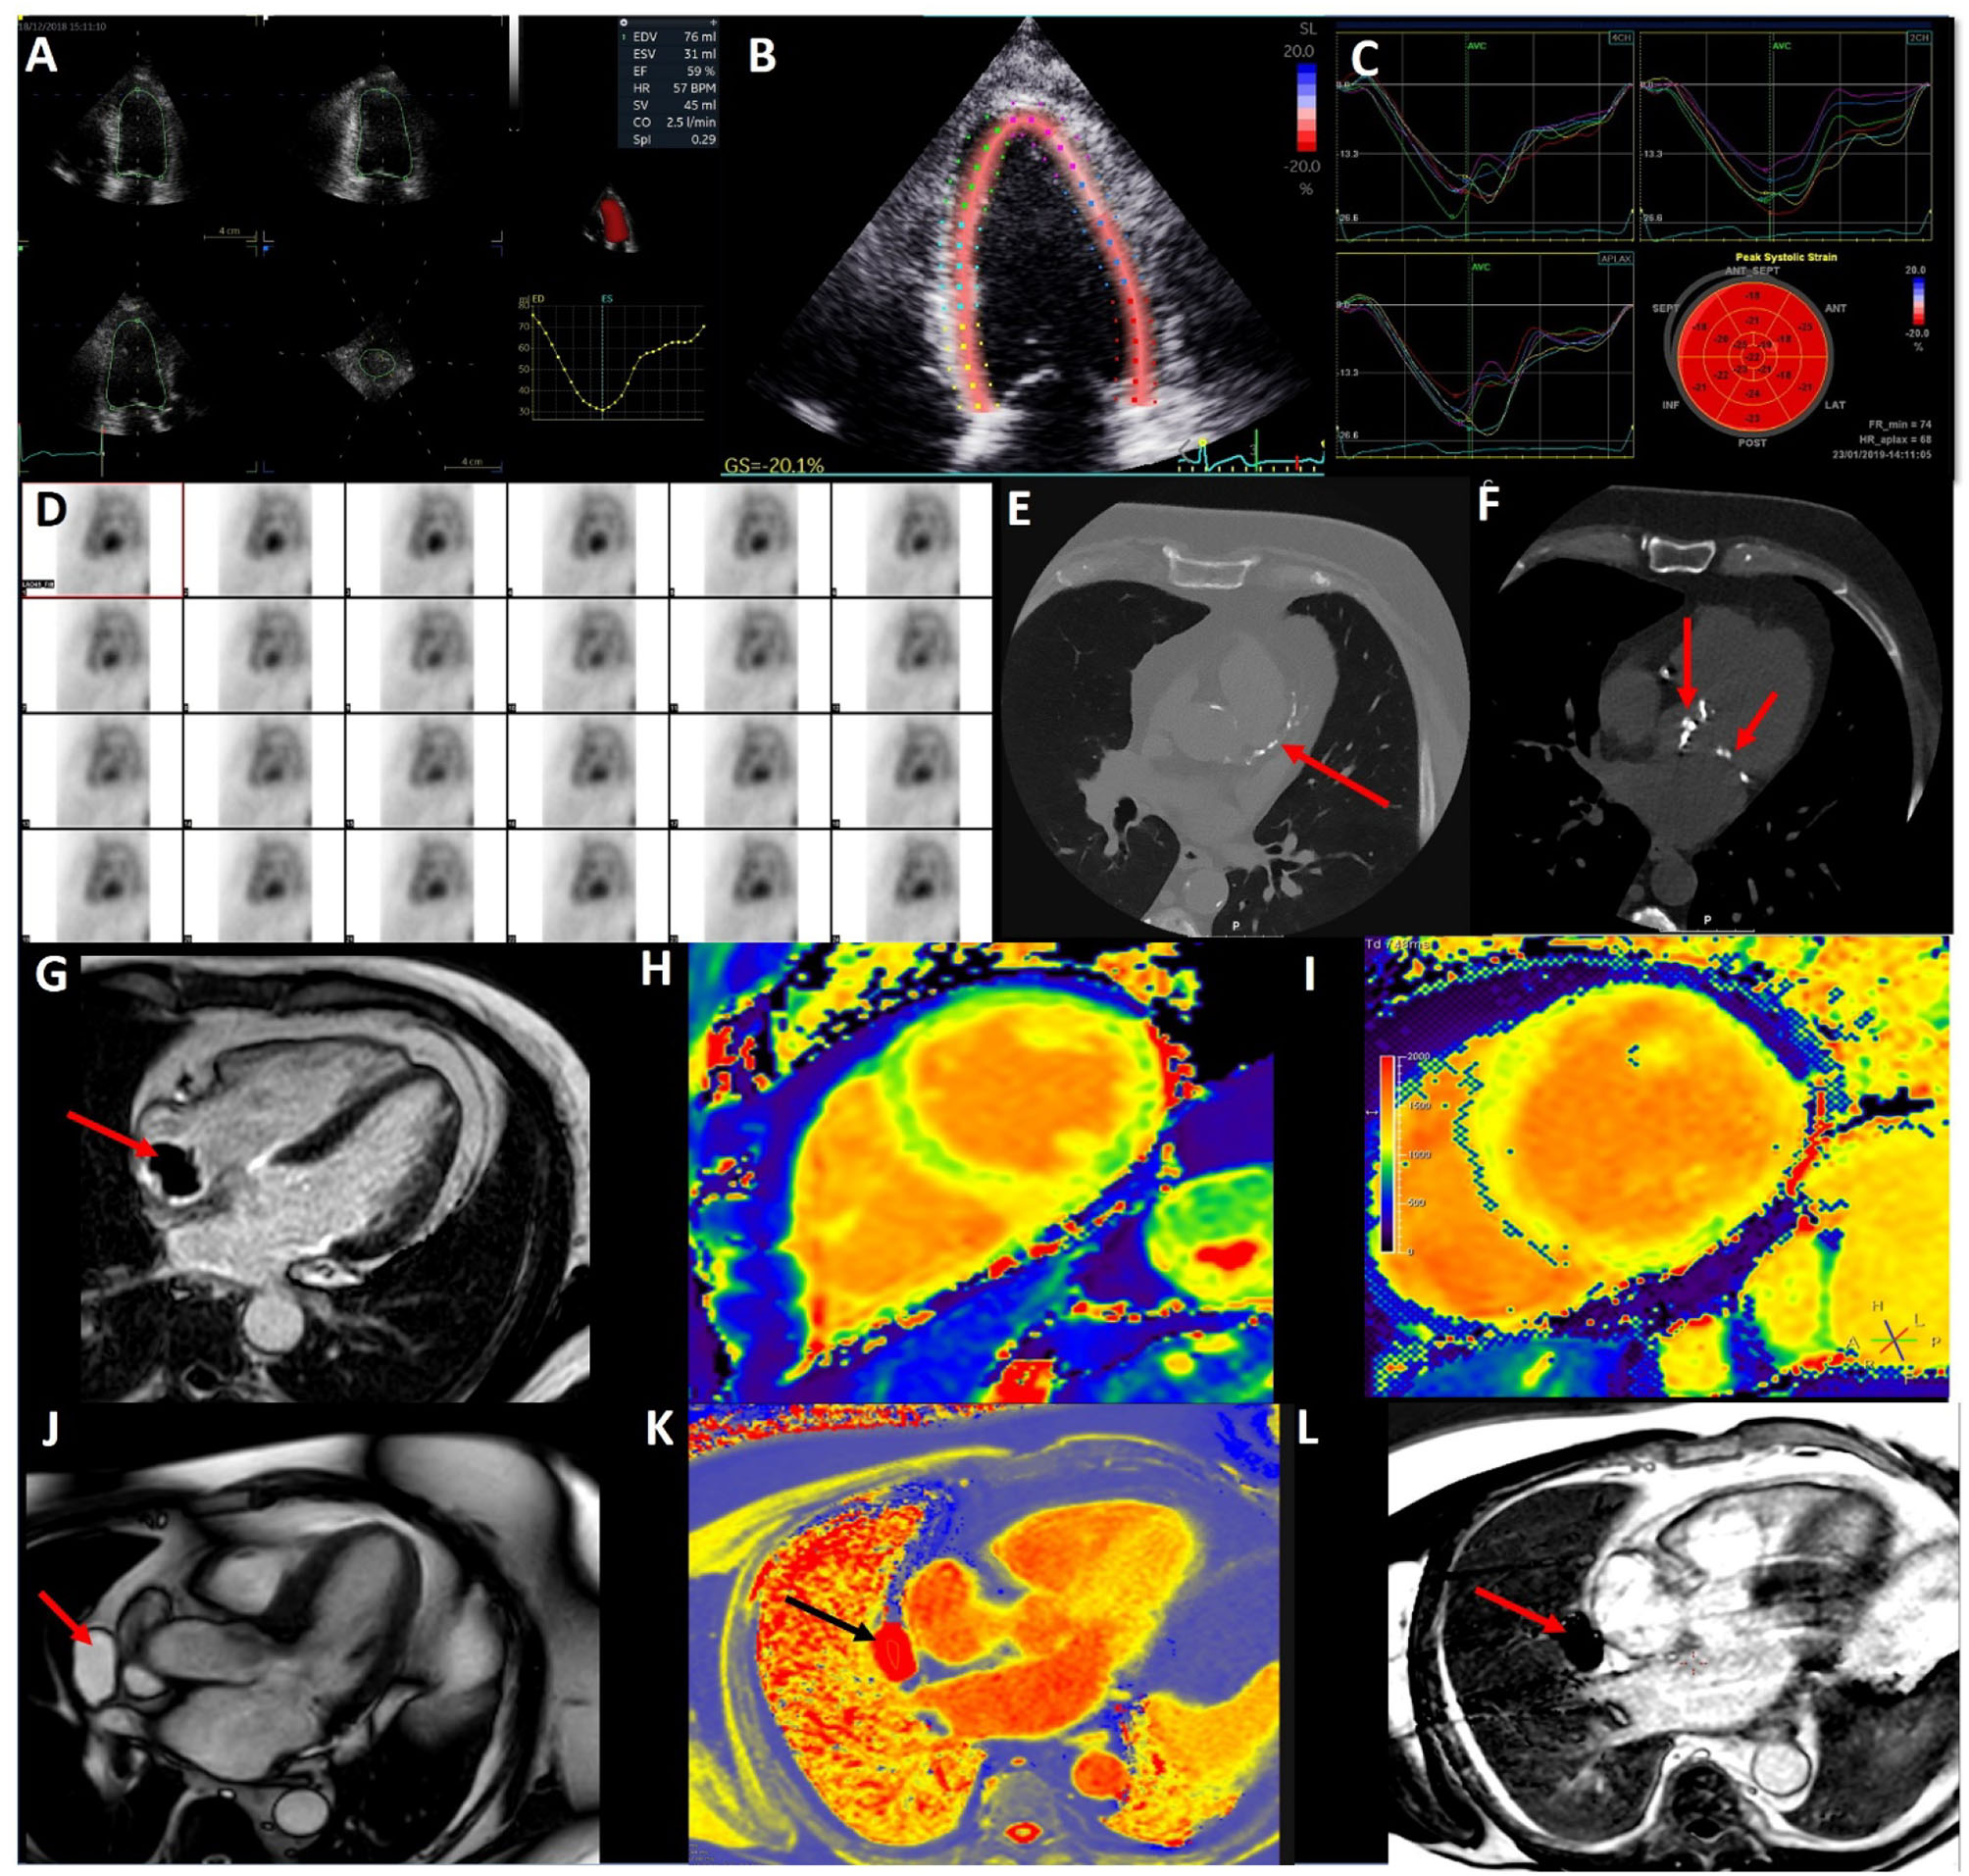

Speckle tracking echocardiography, which has been validated against sonomicrometry and tagged magnetic resonance imaging, has provided accurate angle-independent measurements of myocardial strain. Efforts to standardize myocardial deformation imaging has reduced the variability in this measure compared to other conventional echocardiographic measures of LV systolic function making it ideal for CTRCD (12). Global longitudinal strain (GLS) has been shown to detect LV dysfunction earlier than LVEF in patients receiving cancer therapy and has the potential to guide therapy (13). GLS has better inter and intra observer reproducibility than 2D LVEF by biplane method of disks emphasizing recent society statements that encourage the use of GLS and 3D LVEF in baseline echocardiographic assessments of cancer patients (see Figures 1A–C) (7, 14). GLS and 3D LVEF have the lowest temporal variability with respect to the detection of CRTCD. In a group of hematological cancer patients undergoing anthracycline therapy with normal LVEF, those with a baseline GLS <-17.5%, were associated with a six-times higher increase in cardiac death or symptomatic heart failure (15).

Figure 1

Multi-modal imaging in cardio-oncology. (A) 3D echocardiography to accurately calculate left ventricular volumes and ejection fraction. (B) 2D Speckle Tracking Echocardiography of the left ventricle (4 chamber view) for Global Longitudinal Strain. (C) 2D Left Ventricular Global Longitudinal Strain curves from 4, 2, and 3 chamber views. (D) Nuclear medicine—Multi-gated blood pool imaging to determine LVEF. (E) CT coronary angiogram demonstrating coronary artery calcium in the left anterior descending artery in a lymphoma survivor. (F) CT coronary angiogram demonstrating radiotherapy related aortic and mitral valve calcification in the same patient. (G) Cardiac Magnetic Resonance (CMR) late gadolinium enhancement with long T1 inversion time demonstrating a thrombus (red arrow) on the end of a Hickman's line in a cancer patient. (H) Normal CMR T1 map (green is normal myocardium). (I) T1 map showed elevated T1 times of the left ventricle in myocarditis. (J) CMR 3Ch cine demonstrating a pericardial mass (red arrow). (K) CMR T1 map highlight the pericardial mass is fill with fluid (black arrow). (L) CMR LGE with long T1 inversion time demonstrating mass (red arrow) is avascular with no enhancement.

The main indication in the current cardio-oncology guidelines for CMR is when there is suboptimal image acquisition and it is preferred over nuclear imaging (6, 7, 16). A key strength of CMR is in the assessment of cardiac masses and inflammatory conditions such as myocarditis, pericarditis, and myopericarditis. This is due to its advantages of multi-planar image acquisition, high spatial resolution, a large field of view, and tissue characterization (45). Tumors and thrombi can be easily differentiated with difference CMR sequence. Tumors tend to be hyperintensity on T2-weighed turbo spin echo, contrast first pass perfusion, and late gadolinium enhancement (LGE), whereas thrombi are hyperintensity with short T1 and hypointensity with long T1 times (see Figure 1G) (46).

Using the forementioned CMR sequences, CMR has a high accuracy for discriminating between benign and malignant lesions, with a good interobserver agreement (47). Figures 1J–L show a pericardial cyst, identified by different CMR techniques. The differentials for the cyst are a pericardial diverticulum and mediastinal mass.

The utility of tissue characterization has becoming increasingly popular over the last decade with the advent of validated software enabling the quantification of T1, T2 mapping, and extracellular volume (ECV) fraction estimation. T1 mapping allows us to detect a range of diffuse pathologies including myocardial fibrosis, myocarditis, cardiac amyloidosis, key aspects of cardio-oncology as well as other pathologies such as storage disorders. T1 measures the longitudinal time to equilibrium post a radiofrequency pulse. The commonest technique to acquire a T1 map is the modified Look-Locker pulse sequence (MOLLI) or “shortened” version known as the shMOLLI (58). Though derived T1 values, the main advantage of these techniques are reduced acquisition time and the shMOLLI in particularly has shorter breath-holds. Native T1 mapping refers to the acquisition of a T1 map without contrast (Figures 1H,I). It is important to note T1 values vary from scanner to scanner and tesla strength (59). The literature on T1 mapping identifying CTRCD are conflicting and limited with the focus being on survivors. The three human studies to date show differing changes in T1 value shortly post anthracycline exposure, with two showing increases in T1 values whilst the other identified a decrease in T1 at 48 h post anthracycline as predictive of CTRCD (54, 60, 61).

Complications of radiotherapy include accelerated atherosclerosis (75). Effects are often identified in the medium to long term. There is a linear radiation dose to risk of CAD relationship, with the excess relative risk of CAD per mean heart Gray dose being 7% (76). Whether radiotherapy leads to an increase visible CAC on CT is contested (77, 78). Figure 1E illustrates extensive CAC in a lymphoma survivor. In regard to acute coronary syndrome, the main risk factor is the volume of LV receiving 5Gy and for each Gy the cumulative incidence increase of acute coronary syndrome is 17% (78). Despite advances in radiotherapy technology and techniques to minimize cardiac complications, close surveillance of radiotherapy therapy patients is warranted 5–10 years post radiotherapy (79).

Valvular Disease

Nuclear Imaging

Multi-gated blood pool imaging (MUGA) was the first imaging modality to be used in cardio-oncology (84). Its primary role historically has been in the measurement of the LVEF (see Figure 1D). MUGA's LVEF measurement was reported superior to 2D echocardiography in 1980's, however, is inferior to CMR (85, 86). Its limitation is the relatively high radiation exposure (5–10 mSV) and the inability to assess other cardiac parameters, has led to a decline in its usage (7). However, there is a role for 18F fluorodeoxyglucose (18FDG) positron emission tomography (PET)-CT scans particularly in the diagnosis and staging of cancer patients. Inflammation is associated with both cancer and cardiovascular disease. 18FDG-PET can identify cardiac inflammation within atherosclerotic plaque as well as myocardial tissue and valves (87, 88). Retrospective data in patients who have received doxorubicin and a subsequent increase in LV 18FDG uptake, are associated with a decline in LVEF (89). This increased uptake suggests there may be a myocardial inflammation component to CTRCD and warrants further investigation despite its high cost and lower availability. With the increasing use of ICIs myocardial inflammation will become an increasing problem. The limited evidence to date indicates 18FDG-PET does not identify ICI related atherosclerosis, however further investigation is warranted, potentially with more specific tracers for vascular inflammation (87, 90).